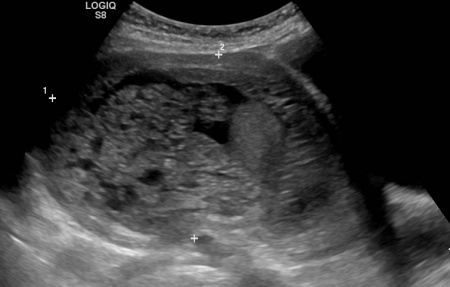

Pregnancy molar partial ultrasound cystic case presentation 2d evidence transabdominal hydropic diffuse degeneration circumscribed placenta structures showing figure